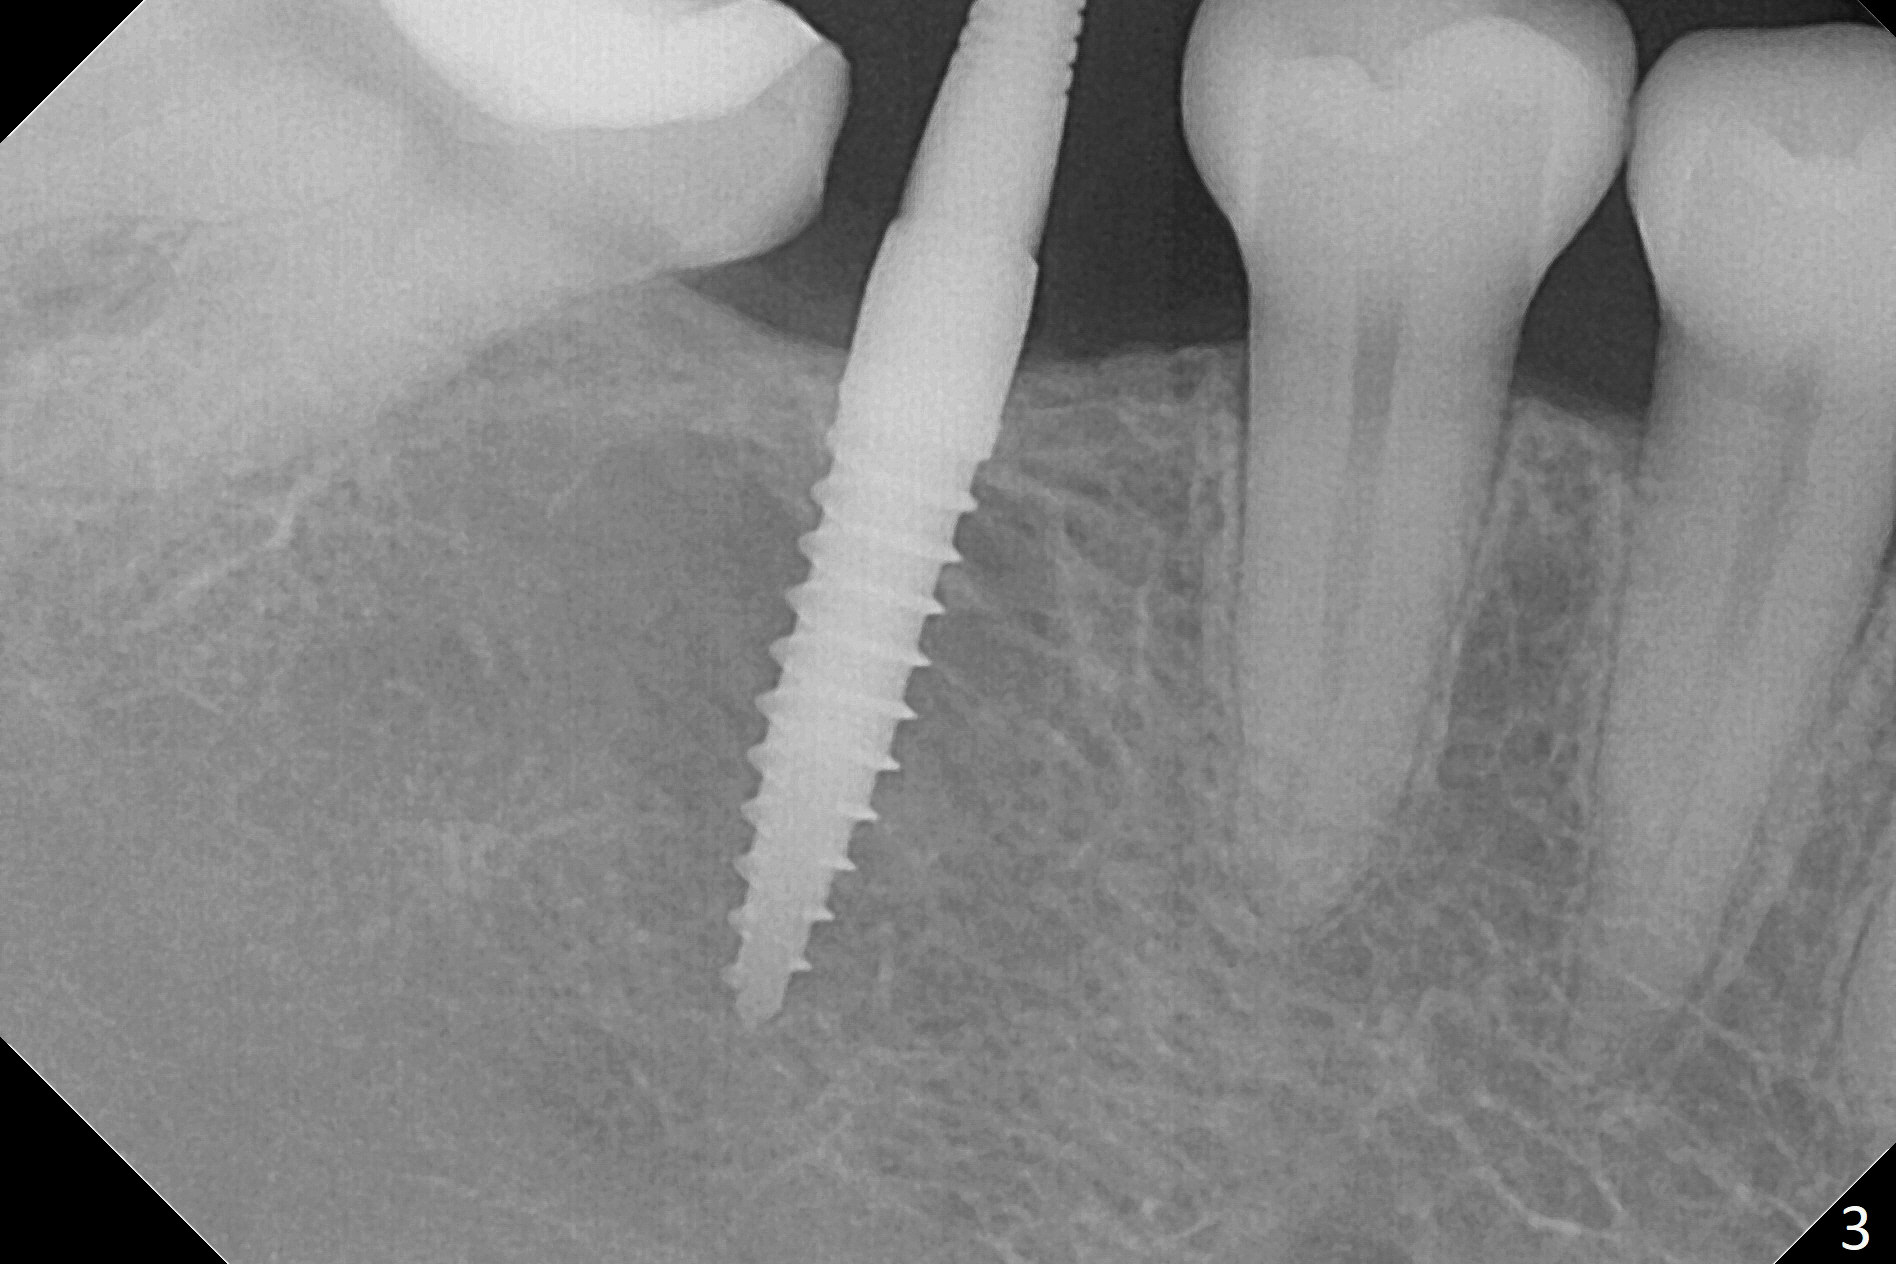

When a 1.2x12 mm drill is placed at #30, it passes the bone cavitation (Fig.1 red dashed line (low density)) twice for two-pointed fixation. So does the 3x12(2) mm 1-piece implant (Fig.2,3). The mesial margin of the tooth #31 is further reduced prior to suturing and periodontal dressing. Impression is taken 5 months postop (Fig.4). Residual cement mesial to the crown at #31 is later removed (Fig.5). Since the crowns were made at #30 and 31 at the same time, there appears no food impaction in between (Fig.6, 5.5 months post cementation).